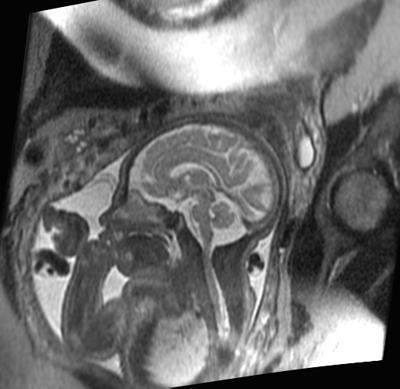

Resonancia magnética en el diagnóstico de malformaciones cerebrales del feto

26 diciembre 2016

En comparación con la ecografía, la RM aumentó la precisión del diagnóstico y modificó los planes de manejo. El estudio fue bien tolerado. The Lancet, 14 de diciembre de 2016